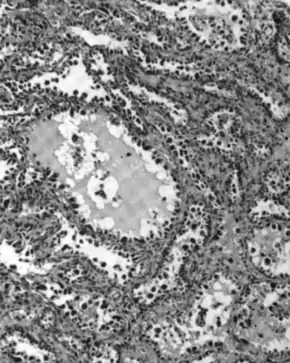

Serous carcinoma

.jpg.webp)

Serous ovarian cancer is the most common type of epithelial ovarian cancer and it accounts for about two-thirds of cases of epithelial ovarian cancer.[28] Low-grade serous carcinoma is less aggressive than high-grade serous carcinomas, though it does not typically respond well to chemotherapy or hormonal treatments.[28] Serous carcinomas are thought to begin in the Fallopian tube.[68][69] High grade serous carcinoma accounts for 75% of all epithelial ovarian cancer.[67] About 15–20% of high grade serous carcinoma have germline BRCA1 and BRCA2 mutations.[67] Histologically, the growth pattern of high grade serous carcinoma is heterogenous and has some papillary or solid growth patterns.[67] The tumor cells are atypical with large, irregular nuclei.[67] It has a high proliferation rate.[67] 50% of the time, serous carcinomas are bilateral, and in 85% of cases, they have spread beyond the ovary at the time of diagnosis.[70]

Serous Tubal Intraepithelial Carcinoma (STIC) is now recognized to be the precursor lesion of most so-called ovarian high-grade serous carcinomas.[70] STIC is characterised by

- Abnormal p53 staining

- Ki67 proliferation index in excess of 10%

- Positive WT1 (to exclude metastases)[70]